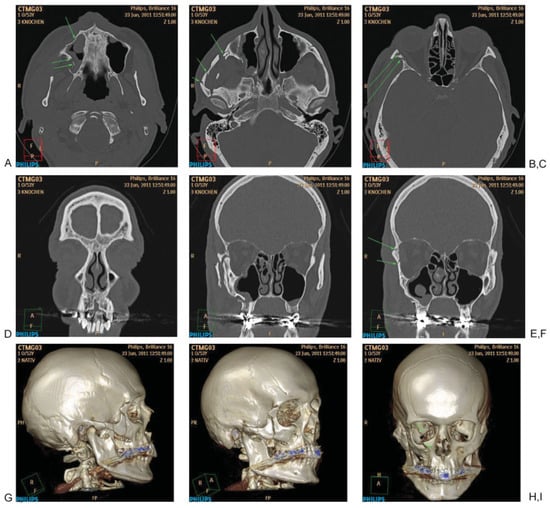

Figure 2. Systematic analysis of a midfacial fracture. (A) Axial slice: evaluation of the lower central midface with fracture of the zygomatic alveolar crest, anterior and dorsolateral maxillary sinus wall (arrows). (B) Axial slice: Involvement of the zygomatic arch with multiple fractures (arrows). (C) Axial Slice: Fracture of the anterior part of the lateral wall (arrows). (D) Two-dimensional coronal reconstruction at level frontogygomatic buttress (no fracture). (E, F) Two- dimensional coronal reconstruction with the fractures at the zygoma and anterior part of the lateral orbital wall and fronto-zygomatic suture (arrows). (G–I) Three-dimensional reconstruction showing the involvement of the right zygoma, intermediate and lower central midface and orbit.

Systematic evaluation of the midface in CT begins with the evaluation of axial slices from caudal to cranial (Figure 2A–C) to detect direct fracture signs, especially in the lower central midface (including alveolar process, caudal part of nasomaxillary buttress), intermediate central midface (including anterior sinus walls), upper central midface (including frontal process maxilla, lacrimal bone and nasal bones). In the axial plane the zygoma and zygomatic arch are evaluated with all its relationships to the central midface. Subsequently, the orbital rims as well as lateral and medial orbital walls are assessed. In a second step coronal 2D reconstructions (Figure 2E,F) are checked for the integrity of the nasomaxillary buttress in the lower and intermediate central midface regions, the frontal process of the maxilla and the nasal bones in the anterior coronal reconstructions (Figure 3). The integrity of the palate and the pterygoid plates should also be checked in the coronal plane, which ideally should be perpendicular to the palate. Furthermore the medial orbital walls, the orbital floors and orbital roofs are well detected in the coronal plane. The orbital apex regions are search for integrity, especially of the optic nerve canal. Additional 2D reconstructions for the orbital floor through the axis of the intraorbital nerve may be useful in detecting displaced fractures with muscle entrapment or retrobulbar hematoma. 3D CT reconstructions may not add significant information for level 2 classification (Figure 2G–I).